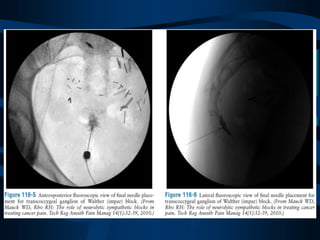

Bloqueo del Ganglio de

Walther (Impar)

ABORDAJE

PRONO